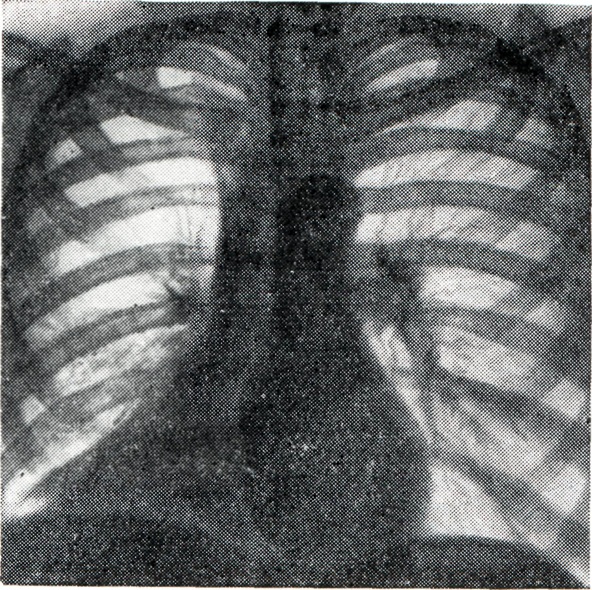

В большинстве случаев при ателектазе наблюдается равномерное затемнение соответствующих отделов легочного поля (рис. 1), смещение органов средостения и корня легкого в сторону поражения, высокое расположение купола диафрагмы и поддиафрагмальных органов на стороне ателектаза, вздутие неизмененных отделов легкого, а иногда — противоположного легкого.

Рис. 1.

Ателектаз верхней доли правого легкого. Массивное затемнение справа рентгенограмма).